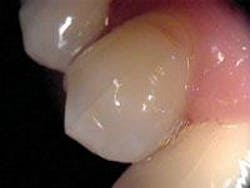

Cracks or fractures can be the result of a variety of habits. Grinding, clenching, and ice chewing over extended periods of time can cause extensive damage to the teeth, with cracks being a common result. Cracks can also be the result of an isolated incident such as biting into an olive pit or bone, or an accident resulting in trauma to the teeth. Although any tooth can be affected by a crack, the mandibular molars are the most prone to fracture. Heavily restored teeth or those with extensive decay are especially subject to cracks. One study evaluated the incidence of CTS in a general practice and found a far higher incidence of CTS in teeth that had the marginal ridge restored than those that had not.3 However, unrestored, noncarious teeth have also exhibited cracked tooth syndrome. Many morphologic, physical, and iatrogenic factors such as deep grooves, pronounced intraoral temperature fluctuation, poor cavity preparation design, and improper selection of restorative materials can predispose posterior teeth to an incomplete fracture (see Figure 1).4